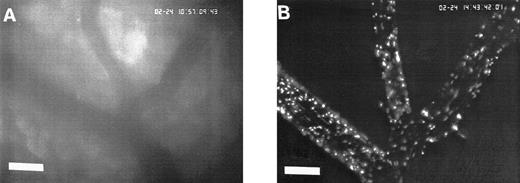

In the physiologic state without I/R, circulating platelets rarely interacted with the microvascular endothelium (Figs1 and 2). Few platelets were observed rolling along the endothelial cell lining of arterioles and postcapillary venules (0 ± 0 and 3 ± 1 platelets/s/mm, respectively). At the same time, only 26 ± 14 and 28 ± 11 platelets were found firmly attached per mm2endothelial cell surface of arterioles and venules, respectively. In contrast, 1.5 hours of ischemia dramatically enhanced platelet-endothelial cell interactions immediately after postischemic reperfusion (Figs 1 and 2). As reported earlier, postischemic platelet accumulation involved arterioles, as well as venules. More than 15 platelets/s/mm vessel diameter were seen rolling along the arteriolar and venular vessel wall, respectively. At the same time, the number of firmly adherent platelets had increased 20- and 12-fold in arterioles and venules, compared with sham-operated animals (Fig 1). Platelet aggregation was a prominent phenomenon. Electron microscopy demonstrated that single or aggregated platelets adhered directly to endothelial cells; obvious defects in the endothelial cell layer were not detected (Fig 3).

Sequence of photographs documenting I/R-induced platelet-endothelial cell interactions in vivo. Using IVM, rhodamine-6G–labeled platelets are visualized within 3 postcapillary venules before ischemia (A), as well as following 90 minutes of ischemia and 30 minutes of reperfusion (B). Few platelets adhere to the venular endothelium before I/R (A); the majority passes the vessel segment without interacting with the endothelial surface. In contrast, a large number of platelets are seen interacting with the endothelium 30 minutes after reperfusion (B). Monitor magnification 450×; bars represent 50 μm.